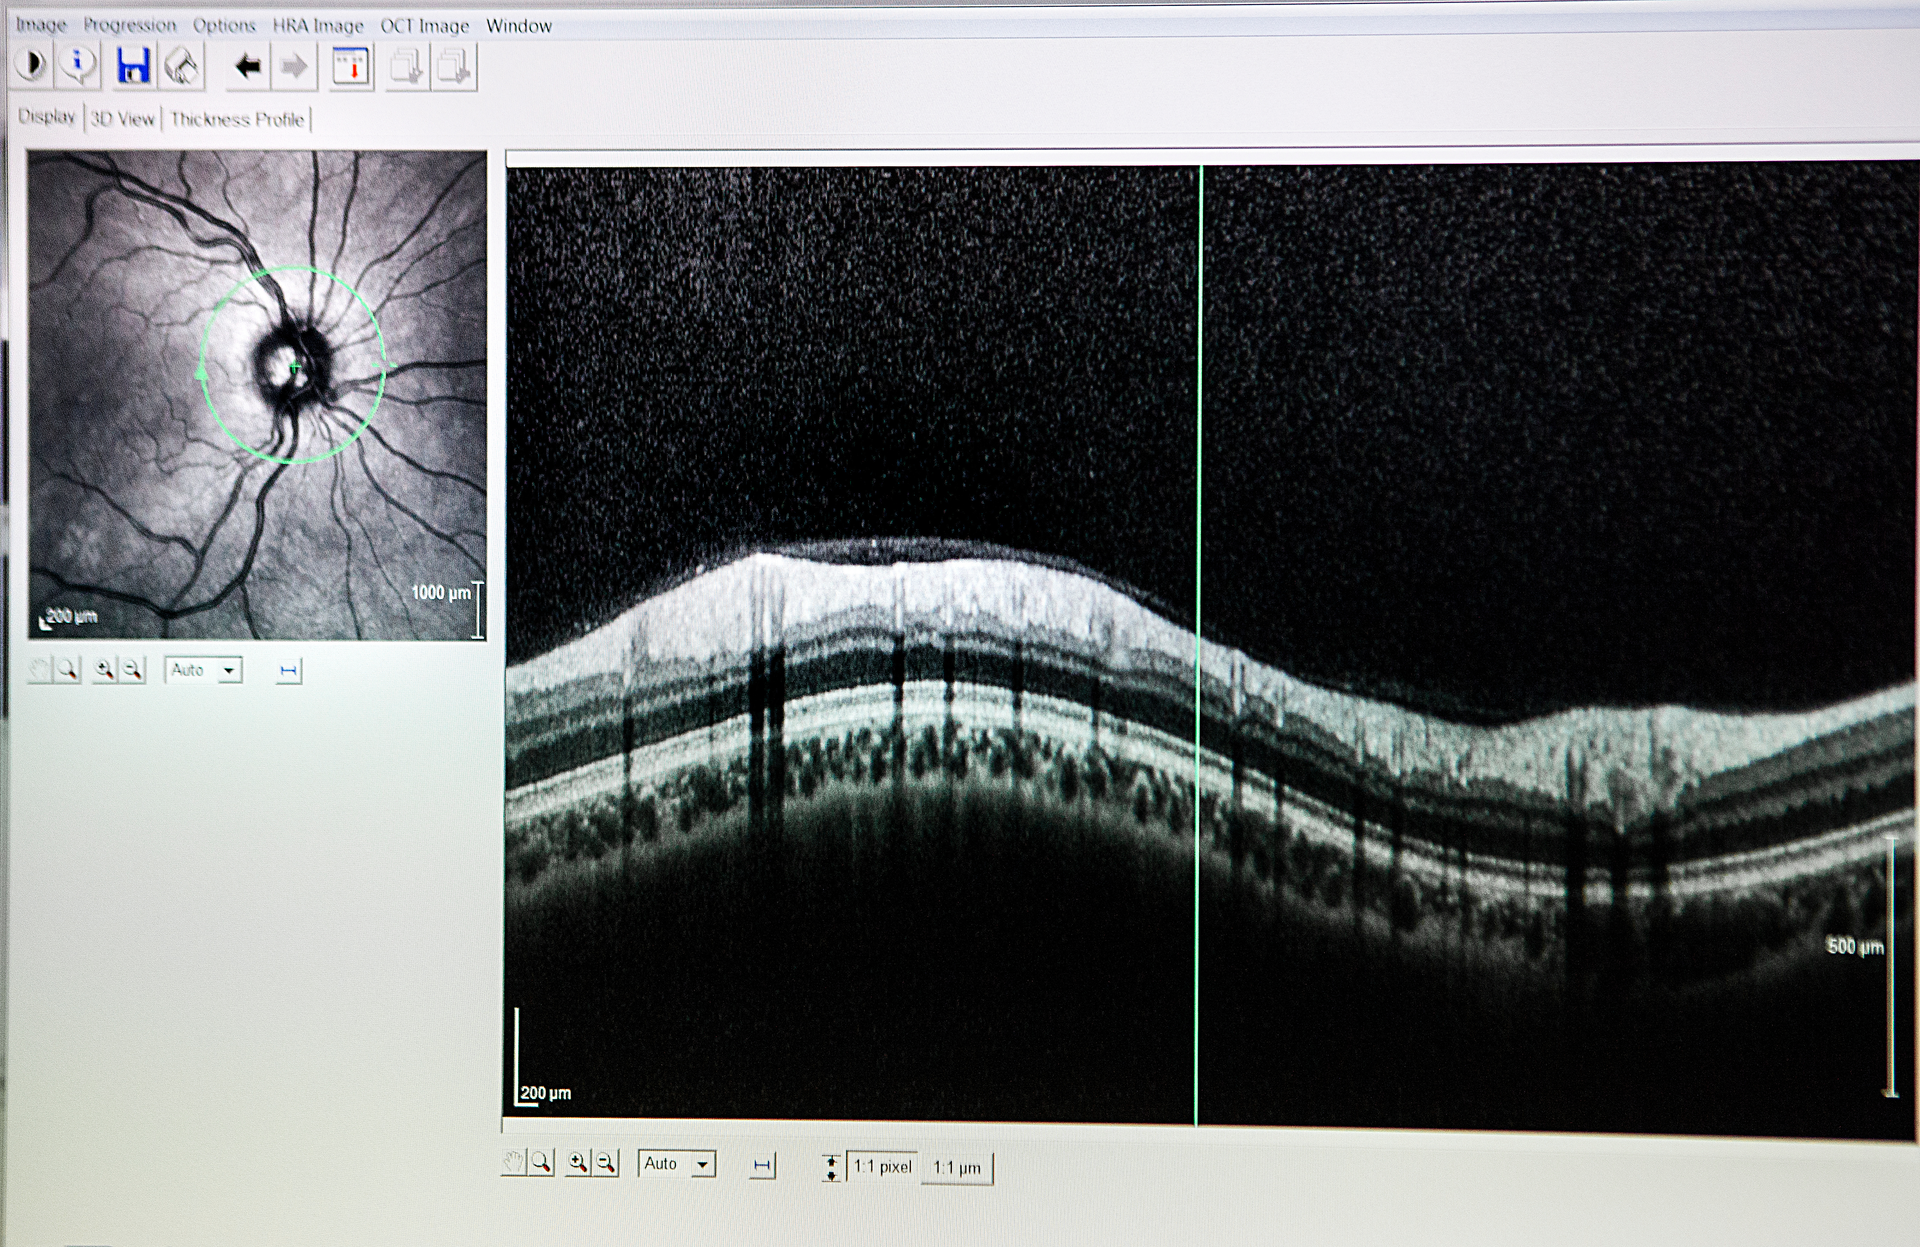

SD-OCT allows ophthalmologists to image the eye to aid the diagnosis of eye diseases, such as glaucoma and age-related macular degeneration (AMD), and to provide in situ imaging during eye surgery procedures. Due to the optically clear imaging pathway through the eye, OCT can easily be used to scan through the tissue layers of the eye.

Many SD-OCT devices on the market are used to image disorders of the retina and the anterior segment of the eye. For example, SD-OCT is used to detect glaucoma, an eye disease that damages the optic nerve due to an increase in pressure from fluid buildup.

When using SD-OCT, a thickness map of the retinal nerve fiber layer, as seen in Figure 4, can be formed to understand the severity of glaucoma and track its progression.1 SD-OCT can also be paired with surgical platforms such as laser eye surgery or phacoemulsification procedures to provide real-time images for the surgeon.